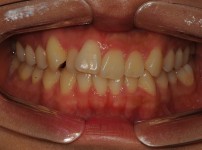

BEFORE

AFTER

클릭 해주세요.

앞니 벌어짐

치아교정